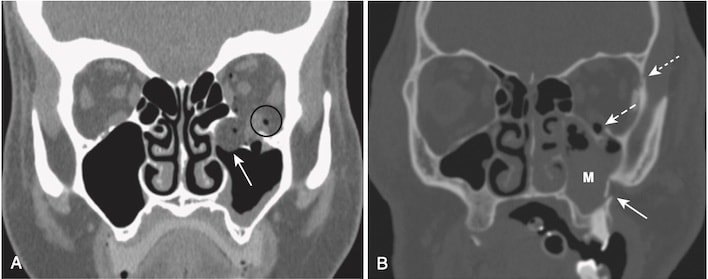

- Gãy xương ổ mắt thường gặp nhất là gãy bung ra/bùng vỡ (blow-out fracture) (Hình 7), được tạo ra do tác động trực tiếp lên ổ mắt (ví dụ, một quả bóng chày đập vào mắt) và gây ra sự gia tăng đột ngột áp lực trong ổ mắt dẫn đến gãy của sàn ổ mắt dưới (vào trong xoang hàm trên/maxillary sinus) hoặc thành trong của ổ mắt (vào trong xoang sàng/ethmoid sinus). Đôi khi cơ thẳng dưới có thể bị kẹt trong chỗ gãy, dẫn đến hạn chế nhìn lên trên và nhìn đôi.

- Nhận biết gãy bung ra ổ mắt (xem Hình 7, A):

- Khí thũng ổ mắt. Không khí trong ổ mắt thông với một trong các xoang chứa không khí lân cận, hoặc xoang sàng hoặc xoang hàm trên

- Gãy xương qua thành trong hoặc sàn của ổ mắt

- Kẹt mỡ và / hoặc cơ ngoại nhãn, đi xuống dưới như khối mô mềm vào đỉnh xoang hàm trên

- Dịch (máu) trong xoang hàm trên

- Gãy ba chân (tripod fracture), thường là do tác động lực mạnh lên gò má, là một dạng gãy xương mặt tương đối phổ biến khác. Loại gãy liên quan đến việc tách gò má (zygoma) khỏi phần còn lại của mặt bằng cách tách đường khớp trán-gò má, gãy sàn ổ mắt và gãy thành ngoài của bên của xoang hàm trên cùng bên (xem Hình 7, B)